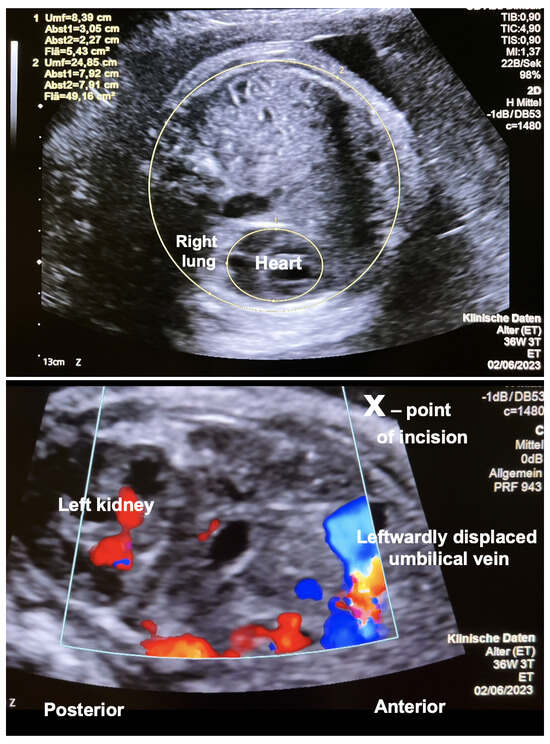

Case Report: Fetoscopic Laparoschisis (FETO-LAP)—A New Therapeutic Route to Explore for Fetuses with Severe Diaphragmatic Hernias

Case